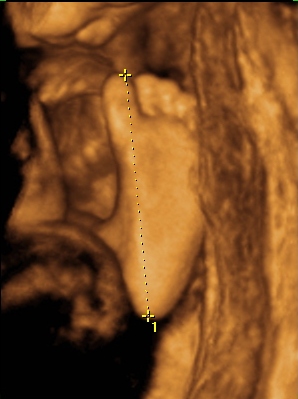

Ma tehát megjártuk a 4D-t meg a cipőboltot. 1,5 órát UHzott a csaj, mert Drága Kistesó nem akarta mutatni magát. Már tornáztam, ettem, ittam épp csak háztömböt nem mentem futni... A végén sikerült 1-2 jobb képet csinálni (azt is csak profilból). Súlya 2 kg (1900valamennyi), mindene 32 hetesnek megfelelő. Minden a helyén van és megvan, hosszú haja van és már most zsíros a Drágám.

No és képek: